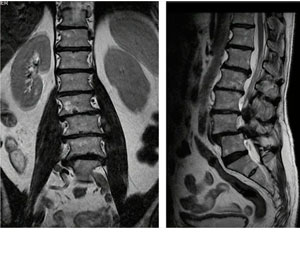

Cifosis rígida toracolumbar (Enfermedad de Scheuermann): varón de 20 años, consulta por dolor toraco lumbar intenso, realizo 4 anos de terapia física y rehabilitación sin éxito. 10 meses Post-operado, se tuvo que realizar varias osteotomías de columna, actualmente sin dolor, realiza actividades cotidianas sin limitaciones.